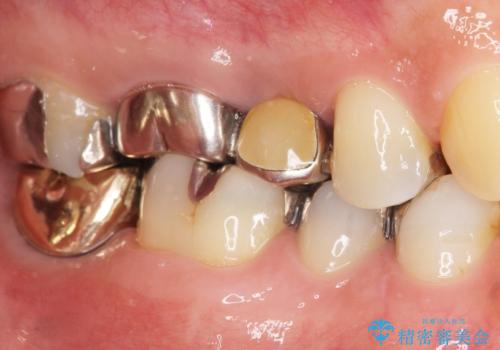

患者様のご希望によりPGA(金白金合金)クラウンによる補綴を行いました。

「金歯は咬み心地もいいし、見た目もカッコイイ!」と喜んで下さいました。

自然な使用感にご満足頂き、他の部位もPGAクラウンによる治療をご希望され現在治療中です。

インプラントの種類:アルファタイト

クラウンの種類:PGA(Platinum Gold cast Alloy・金白金合金)クラウン